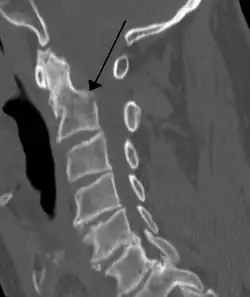

On CT scan or X-ray, a cervical fracture may be directly visualized. In addition, indirect signs of injury by the vertebral column are incongruities of the vertebral lines,[7] and/or increased thickness of the prevertebral space:[8]

![CT scan of normal congruous vertebral lines[7]](./_assets_/Vertebral_lines.png)

![CT scan with upper limits of the thickness of the prevertebral space at different levels[8]](./_assets_/CT_of_prevertebral_space.jpg)